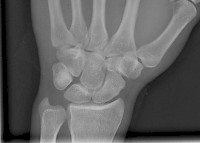

Normalbefund Handgelek ap

Bild: mta-r.de

Die Kahnbeinfraktur (Scaphoidfraktur) ist die wichtigste und zugleich problematischste Handwurzelfraktur. Sie resultiert meist aus einem Sturz auf das extendierte Handgelenk. Standarddianostik ist die Röntgenuntersuchung mit entsprechenden Spezialaufnahmen. Zur weiteren Klärung kommen die Computertomographie (CT) und die Kernspintomographie (MRT) der Handwurzel in Frage.